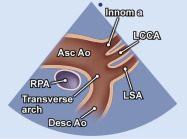

| 2.27. Mặt cắt trên hõm ức ghi hình quai động mạch chủ (video 68 |

||||||||

|

|

|

Cửa sổ siêu âm trên hõm ức

Từ vị trí 12 giờ xoay dần đầu dò hướng về vai trái (vị trí 1 giờ) và nghiêng đầu dò để chùm siêu âm cắt qua núm vú phải và đỉnh xương bả vai trái. |

Động mạch chủ lên (Asc Ao)

Quai động mạch chủ (tranverse arch) Động mạch chủ xuống (Desc Ao) Động mạch vô danh (Innom a) Động mạch cảnh gốc trái (LCCA) Động mạch dưới đòn trái (LSA) |

|||||